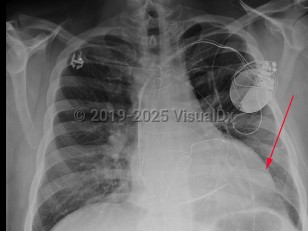

Chest pain, Pleural effusion, 50-59 year old Female

Dilated cardiomyopathyDilated cardiomyopathy

Congestive heart failureCongestive heart failure

Mitral regurgitation